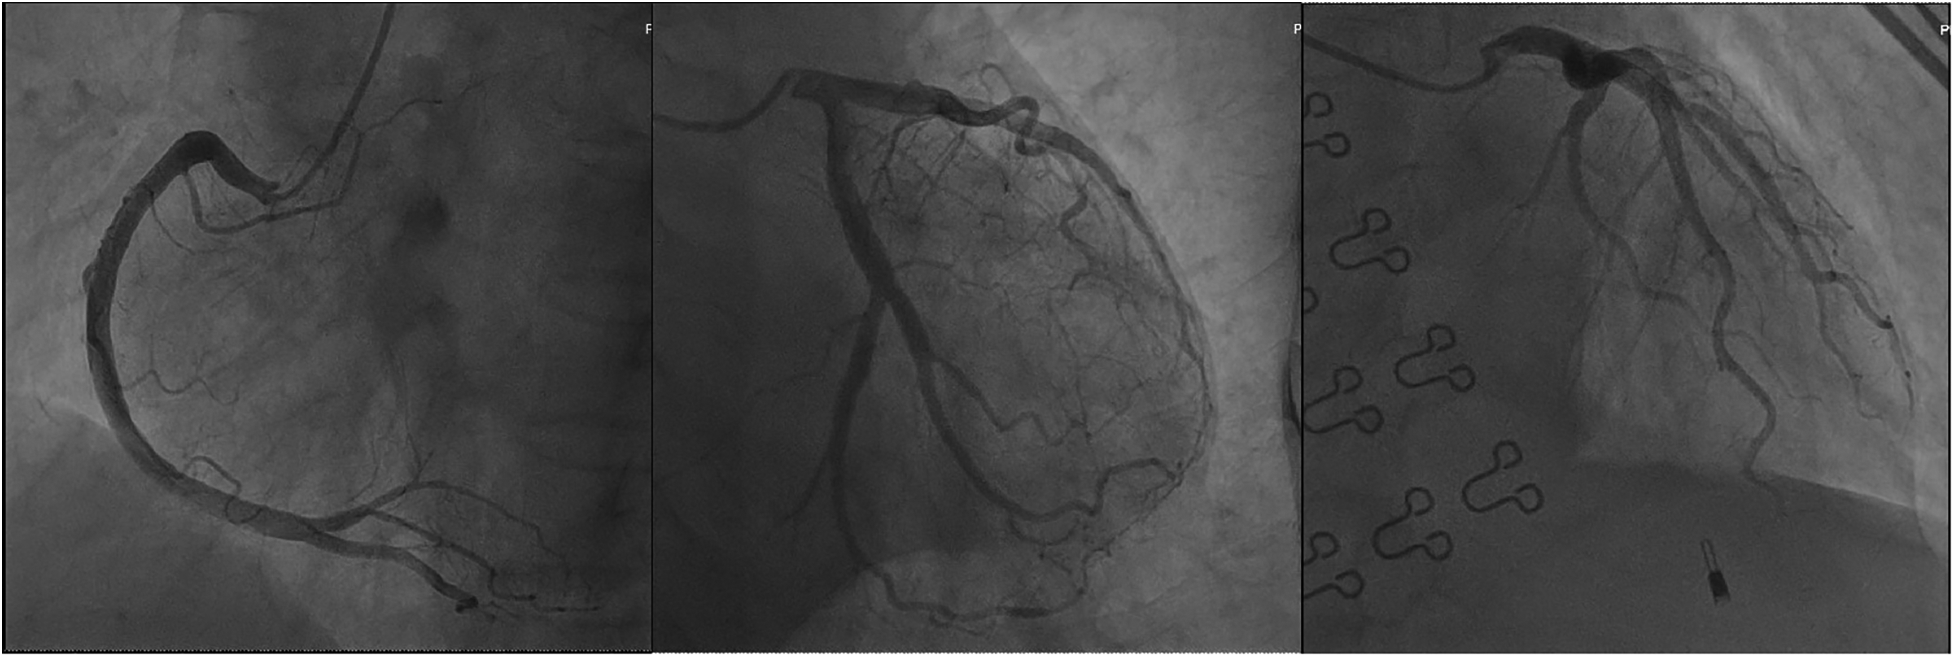

An electrocardiogram showed ST segment elevation of 0.2–0.3 mV in leads II, III, and aVF, and depression of 0.1–0.2 mV in leads I and aVL (Figure 1). Arterial blood gas analysis showed a pH of 7.39, a partial pressure of carbon dioxide of 38.0 mmHg, a partial pressure of oxygen of 42.0 mmHg, an oxygen saturation of 72.1%, and a lactate level of 1.7 mmol/L. The white blood cell count was 6.0 × 109/L (normal range: 3.5–9.5 × 109/L), lymphocyte count was 2.5 × 109/L (normal range: 1.1–3.2 × 109/L), eosinophil count was 0.39 × 109/L (normal range: 0.02–0.52 × 109/L), and eosinophil percentage was 6.5% (normal range: 0.4%–8.0%). Creatine kinase isoenzyme was 1.88 ng/ml (normal range: <3.77 ng/ml), myoglobin was 25 ng/ml (normal range: 25–58 ng/ml), troponin T was 4 pg/ml (normal range: <30 pg/ml), and N-terminal pro-brain natriuretic peptide (NT-proBNP) was 174 pg/ml (normal range: <300 pg/ml). Liver and kidney function tests and coagulation tests were normal. Acute myocardial infarction was suspected, and the patient was treated with subcutaneous injection of heparin 3,000 units, oral ticagrelor tablets 180 mg, and oral aspirin tablets 300 mg. Emergency coronary angiography showed no significant stenosis or thrombus in the coronary arteries (Figure 2). Thrombolysis in myocardial infarction (TIMI) blood flow grade III was observed. After coronary angiography, the patients' heart rate was maintained at around 80 bpm and blood pressure around 100/60 mmHg. Post-angiography electrocardiography showed sinus rhythm, and the ST segment elevation in the inferior leads decreased (Figure 3). A bedside echocardiogram indicated no obvious segmental wall motion abnormalities in the left ventricle.

Figure 2

Coronary angiography revealed no significant coronary artery stenosis or thrombus formation.

Since its first report in 1991, Kounis syndrome has mainly occurred in Southern Europe, with reported incidence rates of 2–19.4 cases per 100,000 inhabitants (5). Currently, there are no reported incidence rates among Asian populations, and only sporadic cases were reported in China. In our patient, coronary angiography did not reveal significant coronary stenosis or acute thrombus formation. Subsequent electrocardiogram showed resolution of ST segment elevation in the inferior leads soon, suggesting coronary artery spasm as the cause, which corresponded to the characteristics of Kounis syndrome Type I. Now, Kounis syndrome is believed to be divided into three types (6). In these three types, patients present with symptoms similar to myocardial infarction, but with varying conditions of the coronary arteries. Type I is characterized by patients having normal coronary arteries, with the coronary artery spasm being caused by an allergic reaction. It is a common cause of non-obstructive myocardial infarction (7). Type II is characterized by patients already having underlying coronary artery atherosclerosis, and the allergic reaction leading to erosion or rupture of the plaque (8). Type III refers to patients who have undergone coronary artery stenting, but experience acute thrombosis due to an allergic reaction. Type III can be further divided into two subtypes, with type IIIa being characterized by thrombus formation within the stent, while type IIIb is characterized by in-stent restenosis (9). Among all Kounis syndrome patients, Type I accounts for 72.6%, while Type II and Type III account for 22.3% and 5.1% (10). The majority of patients (68%) are between 40 and 70 years old, and pediatric cases are relatively rare (11). Males make up 74.3% of the cases.